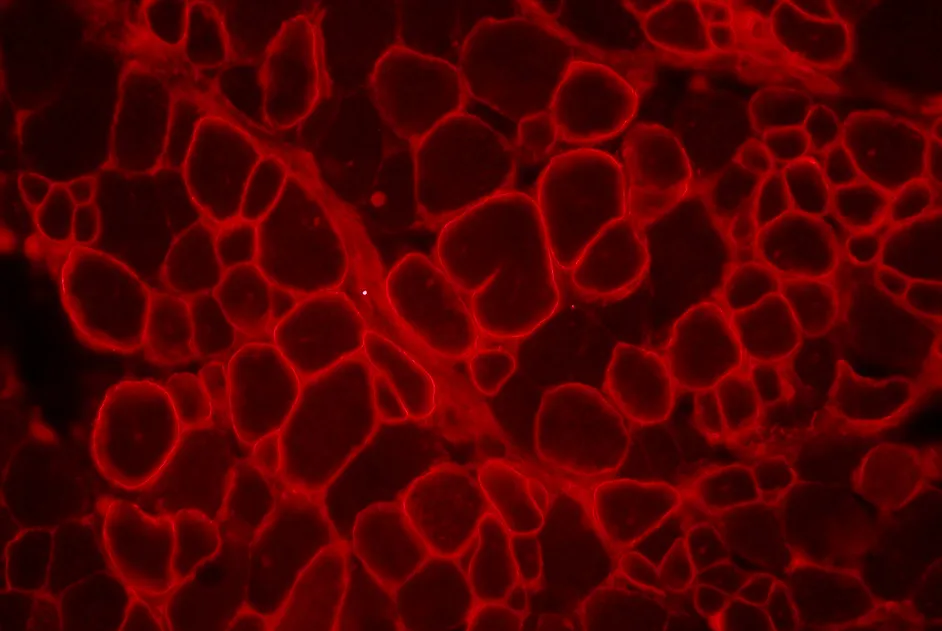

Une équipe franco-américaine a utilisé les TALEN pour restaurer le cadre de lecture dans l’exon 51 du gène de la dystrophine. L’expression de la dystrophine a été restaurée dans les myoblastes et fibroblastes de la peau transfectés en culture.

Une équipe franco-britannique, en collaboration avec la société Cellectis, a corrigé, dans des myoblastes, le gène de la dystrophine ayant perdu les exons 45 à 52 avec des méganucléases. L’expression de la dystrophine complète (incluant les exons 45 à 52) a ainsi été observée dans les myoblastes transfectés.